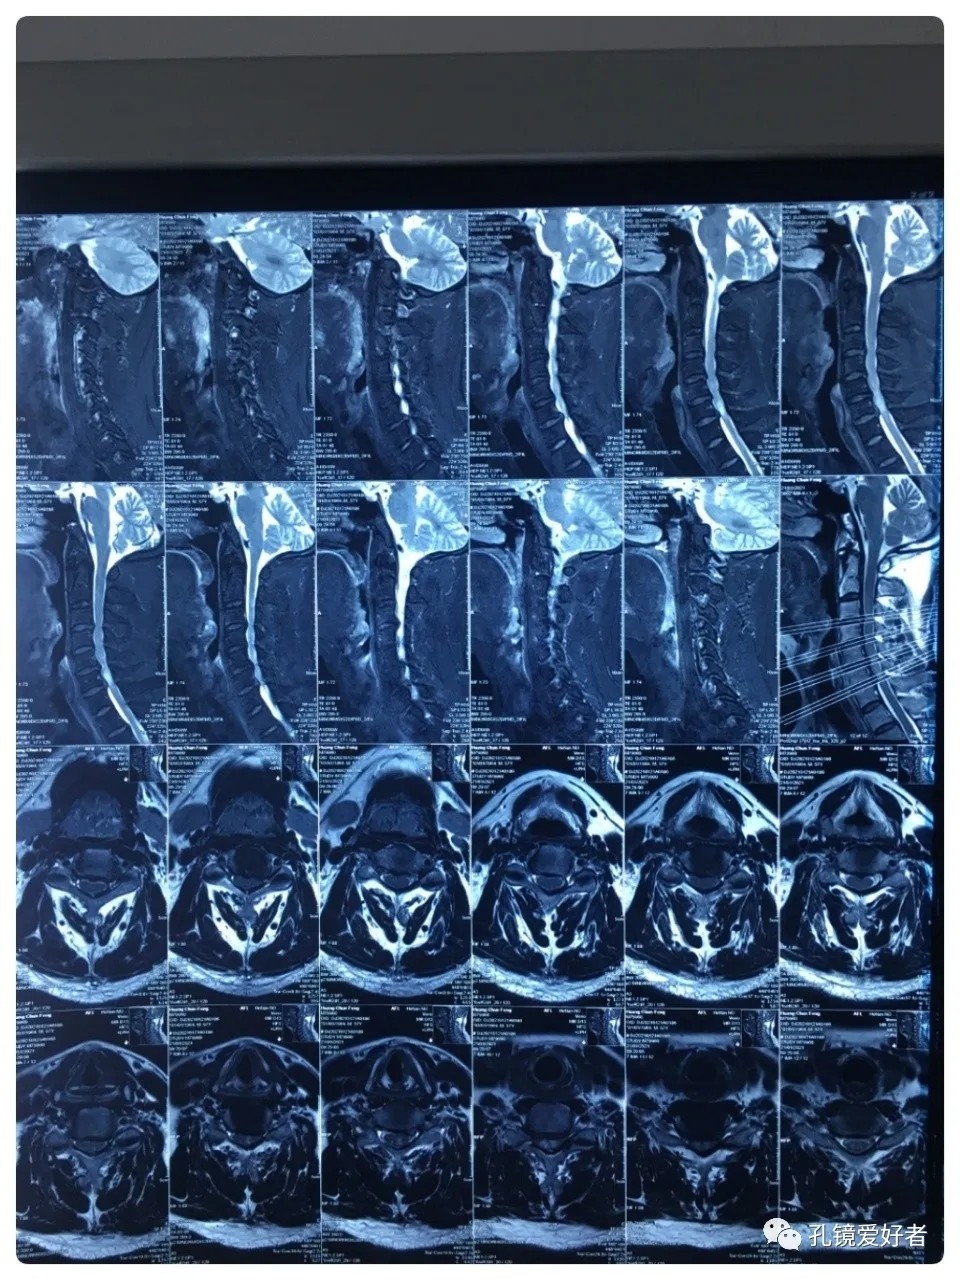

MRI - Sagittal Position

The patient's preoperative imaging data

The PA and lateral and flexion-extension position of cervical spine

Plain CT Scan of The Cervical Spine

CT imaging mainly focused on a plain scan of the cervical spine, and there is no scan on the intervertebral space.